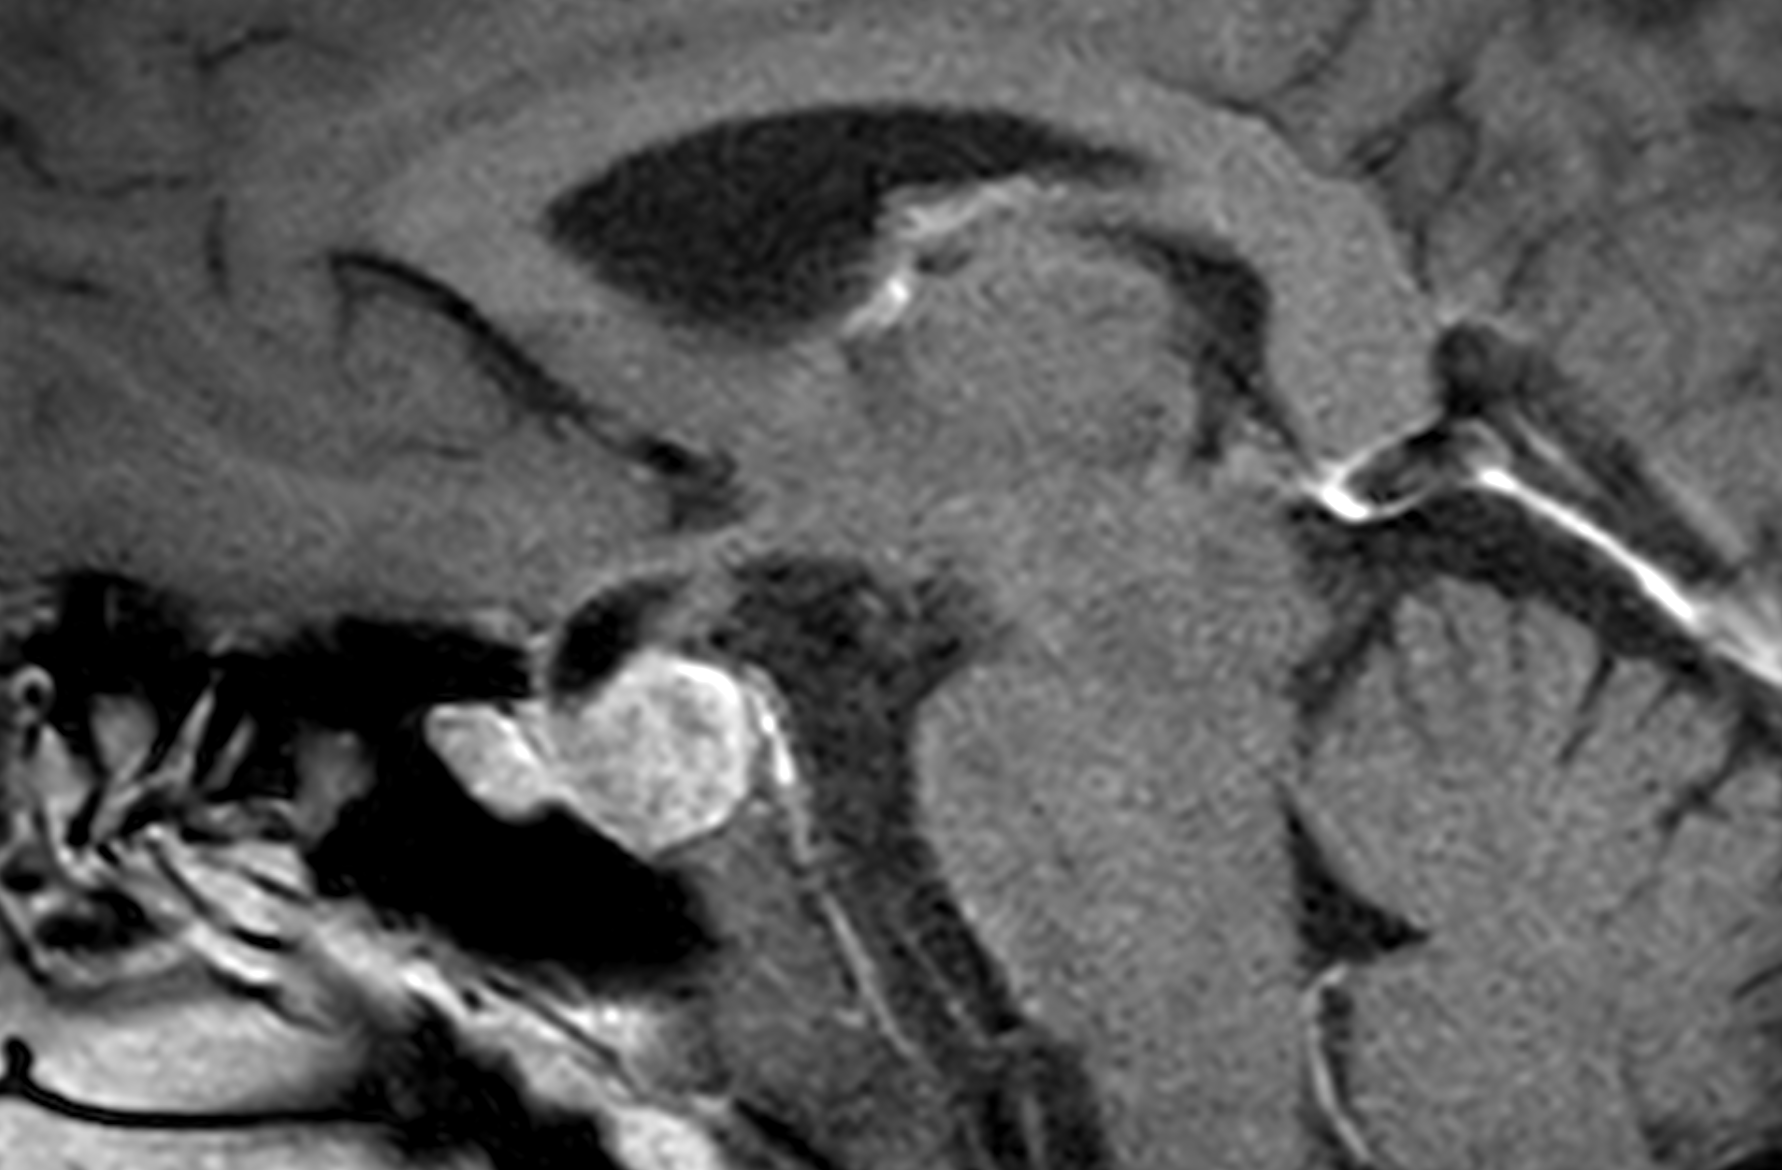

El adenoma de hipófisis es un tumor benigno que afecta la glándula pituitaria y puede provocar una amplia variedad de síntomas endocrinológicos y neurológicos. Gracias al enfoque multidisciplinar y a las técnicas quirúrgicas de vanguardia implementadas en IENSA, se ha conseguido mejorar significativamente el pronóstico y la calidad de vida de los pacientes intervenidos.

Los casos son variados según se trate de adenoma No Funcionantes o Funcionantes, lo que marca la indicación quirúrgica.